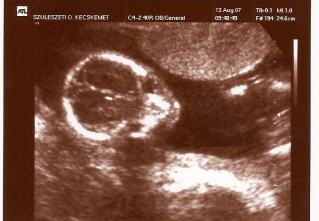

sziasztok, megjöttünk az UH-ról :lol:

Kép

íme Barni ufó-arca :lol:

BPD: 44 mm

AC: 150 mm

FL: 28 mm

HC: 163 mm

OFD: 56 mm

Súlybecslés: 313 g

Hum: 25 mm

és minden más rendben, egyedül a lepényem kicsit mélyebben fekszik, azt mondta a vizsgáló, hogy ne parázzak, a következőn már biztosan az is rendben lesz...

na egy kismama meg a nem parázás :?: :!: :P

22-23 hét körül megejtünk egy 4D UH-ot, akkor már kerekedik a pofija :lol:

Vörösbegy: a képen ez a kis buksija???:) Lehet, hogy hülye kérdés, de ilyenkor hol van a többi része? :oops:

Sagi: egy egy sík, a többi része "lejjebb" volt...a jobb oldalon látszik a két lába, a térdei...